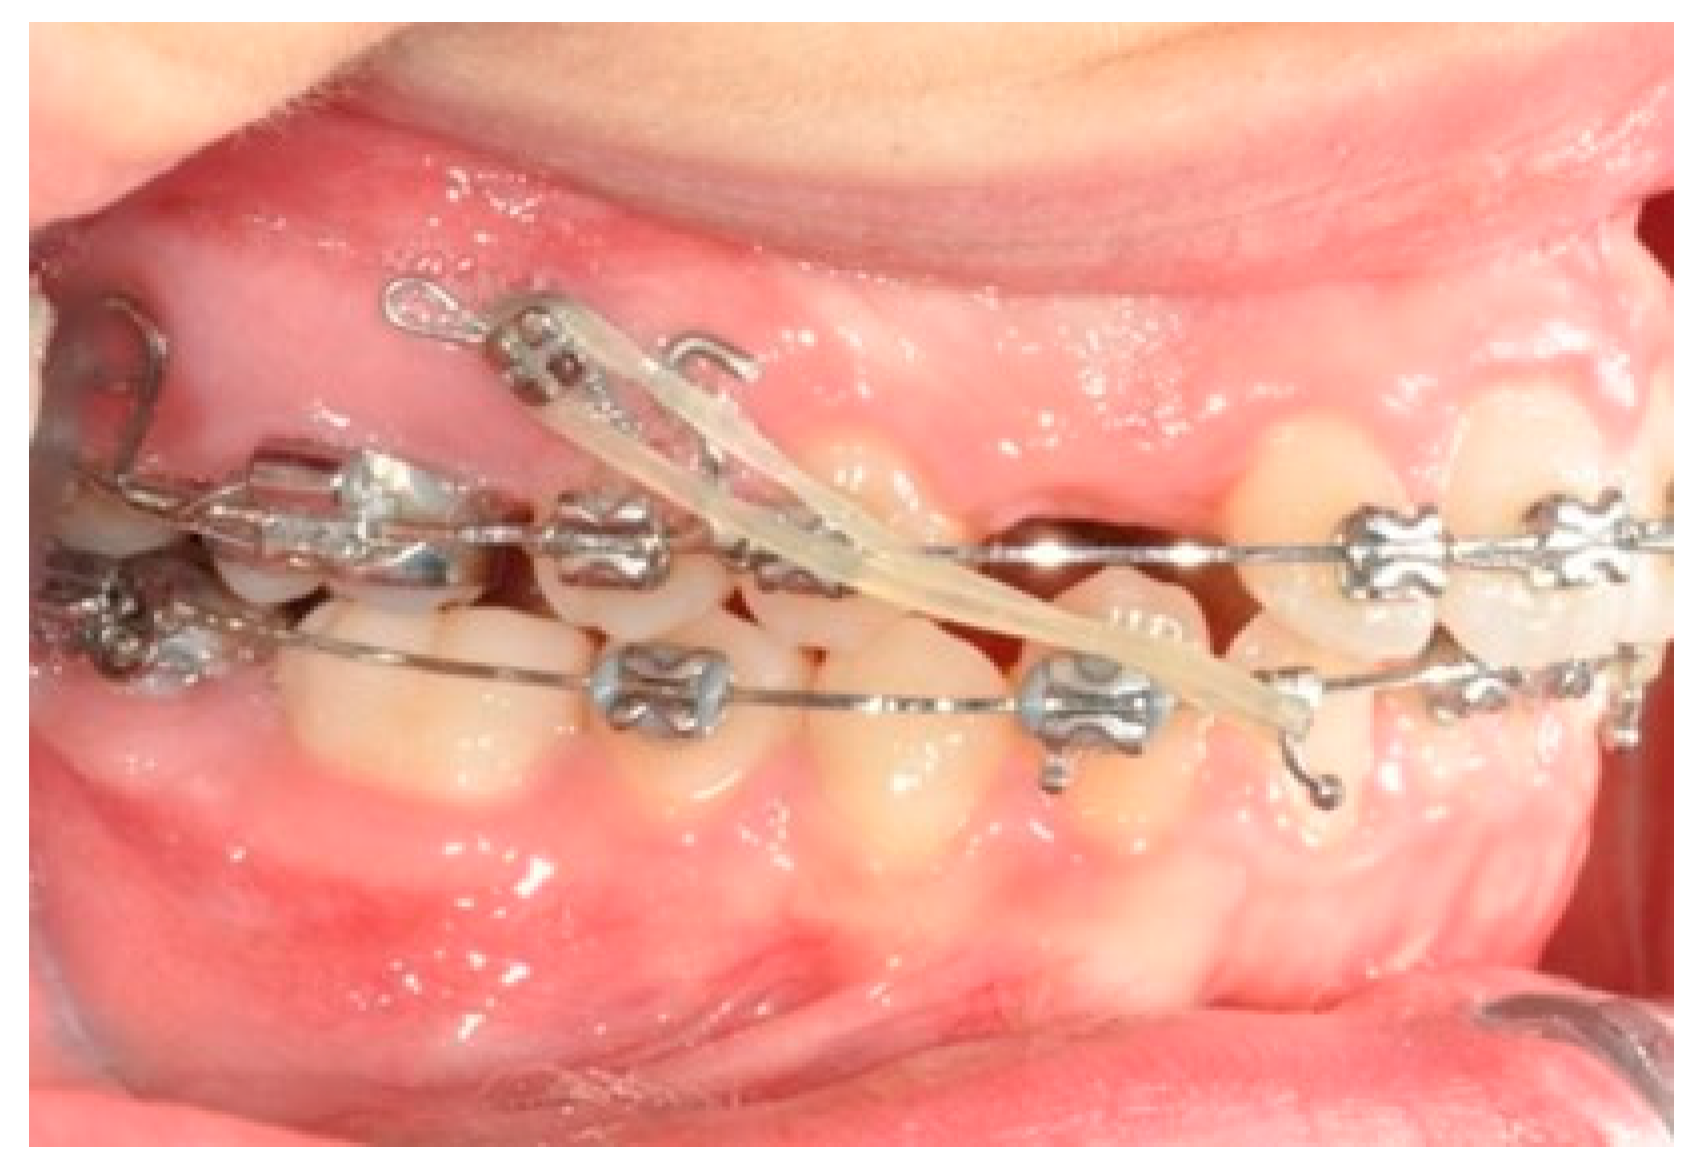

2.3. Canine and Incisor Distalization